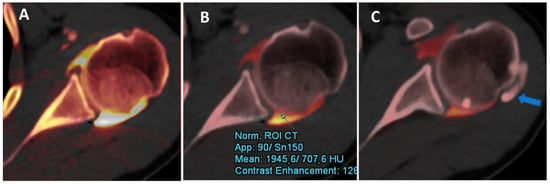

Figure 2.

DECTA iodine map images. The iodine map from DECT can be used to optimize the dilution and visualization of contrast material injected and to differentiate contrast from calcifications. In this case, the axial iodine map DECTA image (A) shows a poorly diluted contrast, creating some artifacts near the posterior labrum. By normalizing contrast material to the density of the less diluted dependent area of the articular cavity (ROI), it is possible to improve the visualization of the labrum and cartilage, avoiding artifacts (B). Some calcifications (arrow in (C)) can be clearly depicted in the same patients.

Figure 3.

Potential pitfalls of DECTA. The sagittal reconstructed 1 mm iodine map from DECTA of the shoulder (A) shows an air bubble coming from injection in the sub-acromial space in a complete rotator cuff rupture (arrow). In the same patient (arrow on (B)), there is an ovoid dense image simulating a calcification in a dependent position. On sagittal high KeV VMI reconstruction (C), there is a complete subtraction of the area of highly concentrated contrast material (arrow).